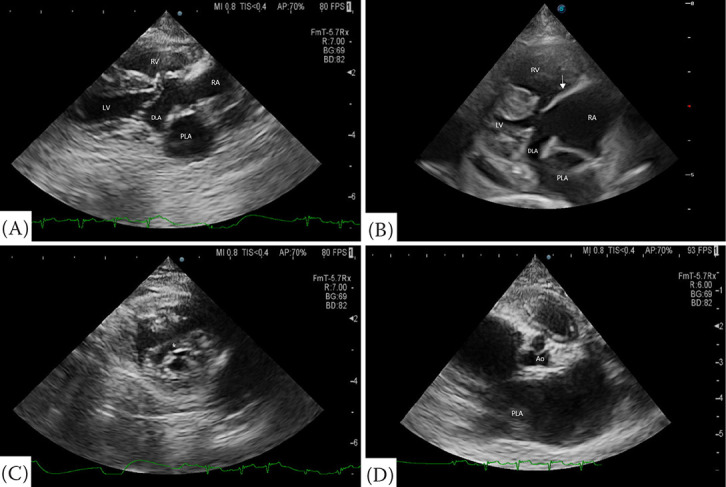

一只6岁的雌性绝育土耳其安哥拉猫因呼吸急促而被转诊。该患者两年前在当地医院进行健康检查时被诊断为心脏肥大。呼吸急促发生在一年前。体格检查时,患者呼吸频率为每分钟72次,收缩压为70 mmHg。胸片显示严重的心脏肥大,左心房(LA)增大,右心房(RA)增大,右心室增大,肺动脉和肺静脉扩张。在右、左颅肺叶可见肺泡型。超声心动图显示一层膜将左心室分为两个腔室,下房间隔缺损,前或后三尖瓣(TV)伸长。然而,没有观察到间隔电视。在心脏收缩期,经房间隔缺损证实血流量从左心房流向右心房。舒张期,血流量从左室到左室被证实。这些结果提示心房三房性心绞痛(CTS)合并部分房室间隔缺损(AVSD)。本报告描述了超声心动图诊断CTS合并部分AVSD的猫。

A 6-year-old female neutered Turkish Angora cat was referred due to tachypnoea. The patient was diagnosed with cardiomegaly at a local hospital during a health screening two years ago. Tachypnoea occurred one year ago. On physical examination, the patient presented with a respiratory rate of 72 breaths per minute and a systolic blood pressure of 70 mmHg. Thoracic radiographs revealed severe cardiomegaly, left atrium (LA) enlargement, right atrium (RA) enlargement, right ventricular enlargement, and dilation of pulmonary arteries and veins. An alveolar pattern was identified in the right and left cranial lung lobes. Echocardiography revealed a membrane that divided the LA into two chambers, a defect in the lower atrial septum, and elongation of anterior or posterior tricuspid valves (TV). However, septal TV was not observed. During systole, blood flow from LA to RA was confirmed through a defect in the atrial septum. During diastole, blood flow from LA to left ventricular was confirmed. These findings suggest cor triatriatum sinister (CTS) with partial atrioventricular septal defect (AVSD). This report describes echocardiographic diagnosis of CTS with partial AVSD in a cat.